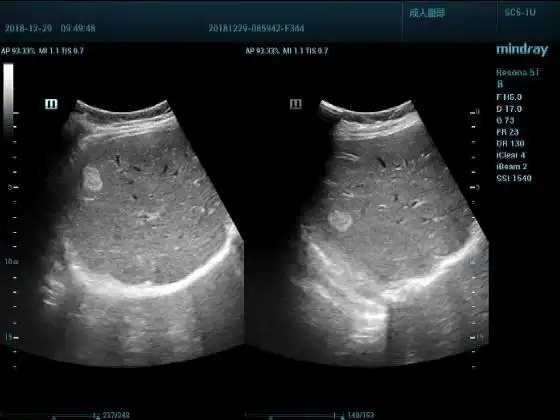

超声入门贴947多发性肝血管瘤

肝血管瘤?还是ca?

肝脏丨血管瘤

大家见过低回声的肝血管瘤吗? - 超声医学讨论版 - 爱爱医医学论坛

肝巨大血管瘤